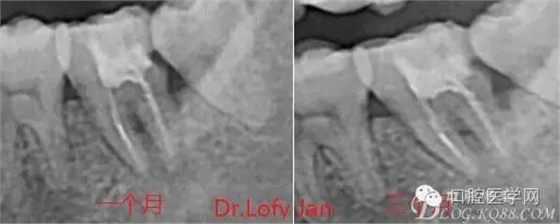

曲面斷層片在未試尖根管治療中的病例整理

前言:自己做的一些曲面斷層片在未試尖根管治療中的病例整理,發(fā)現(xiàn)問題很多包括自身的,技術(shù)的,還有設(shè)備的問題,予以總結(jié)整理并期待進(jìn)一步提高。

病例分析:曲面斷層片在x線輔助診斷與檢查中目前大多數(shù)文獻(xiàn)和著作都建議只能作為初診拍片檢查手段,不能作為終末疾病的確診與手術(shù)療效的評(píng)價(jià)指標(biāo),臨床大部分中小型門診都因?yàn)樵O(shè)備不齊全導(dǎo)致信息偏差很大。